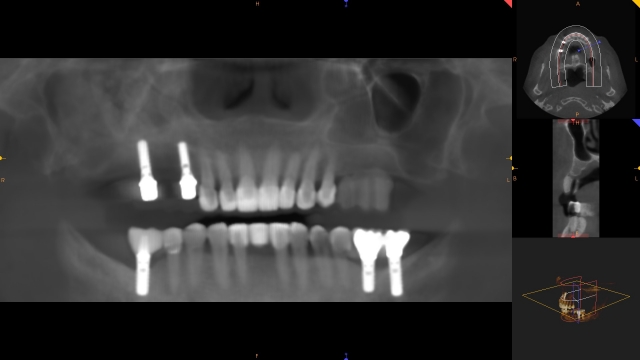

If the support comes in the form of an implant, the next job is to help my surgeon understand the optimal implant position in order to create the best restorative outcome. The surgeon’s job is to tell me if that is possible and what needs to be done to get there.

The best information for both the restorative doctor and the surgeon comes from a radiographic template that transfers the desired tooth position to the mouth in a form that can be included in a CBCT. There are many ways to create a radiographic template and, regardless of which you choose, it should satisfy these basic requirements:

Radiographic templates are not surgical guides, they are a means to determine if the desired implant position is possible in a given situation and, if not, can help the surgeon make decisions on how to augment a surgical site. However, sometimes a radiographic template can be converted to a surgical guide if the desired implant position that is represented by the guide does not change after seeing the scan.

The patient can be instructed in how to insert the appliance and can take it with them if they are having the CBCT done outside of your office. The end result will give you and the surgeon a more clear understanding of potential implant positions. The hole that is drilled through the teeth will be radiolucent on the CBCT and serve as an indicator of possible implant angulation that can be corrected by the surgeon as the case is planned.

If the CBCT exam shows that the proposed position is acceptable and that no grafting is needed, this radiographic guide can be converted to a surgical guide by simply inserting metal sleeves that are the appropriate diameter to the drills the surgeon prefers.